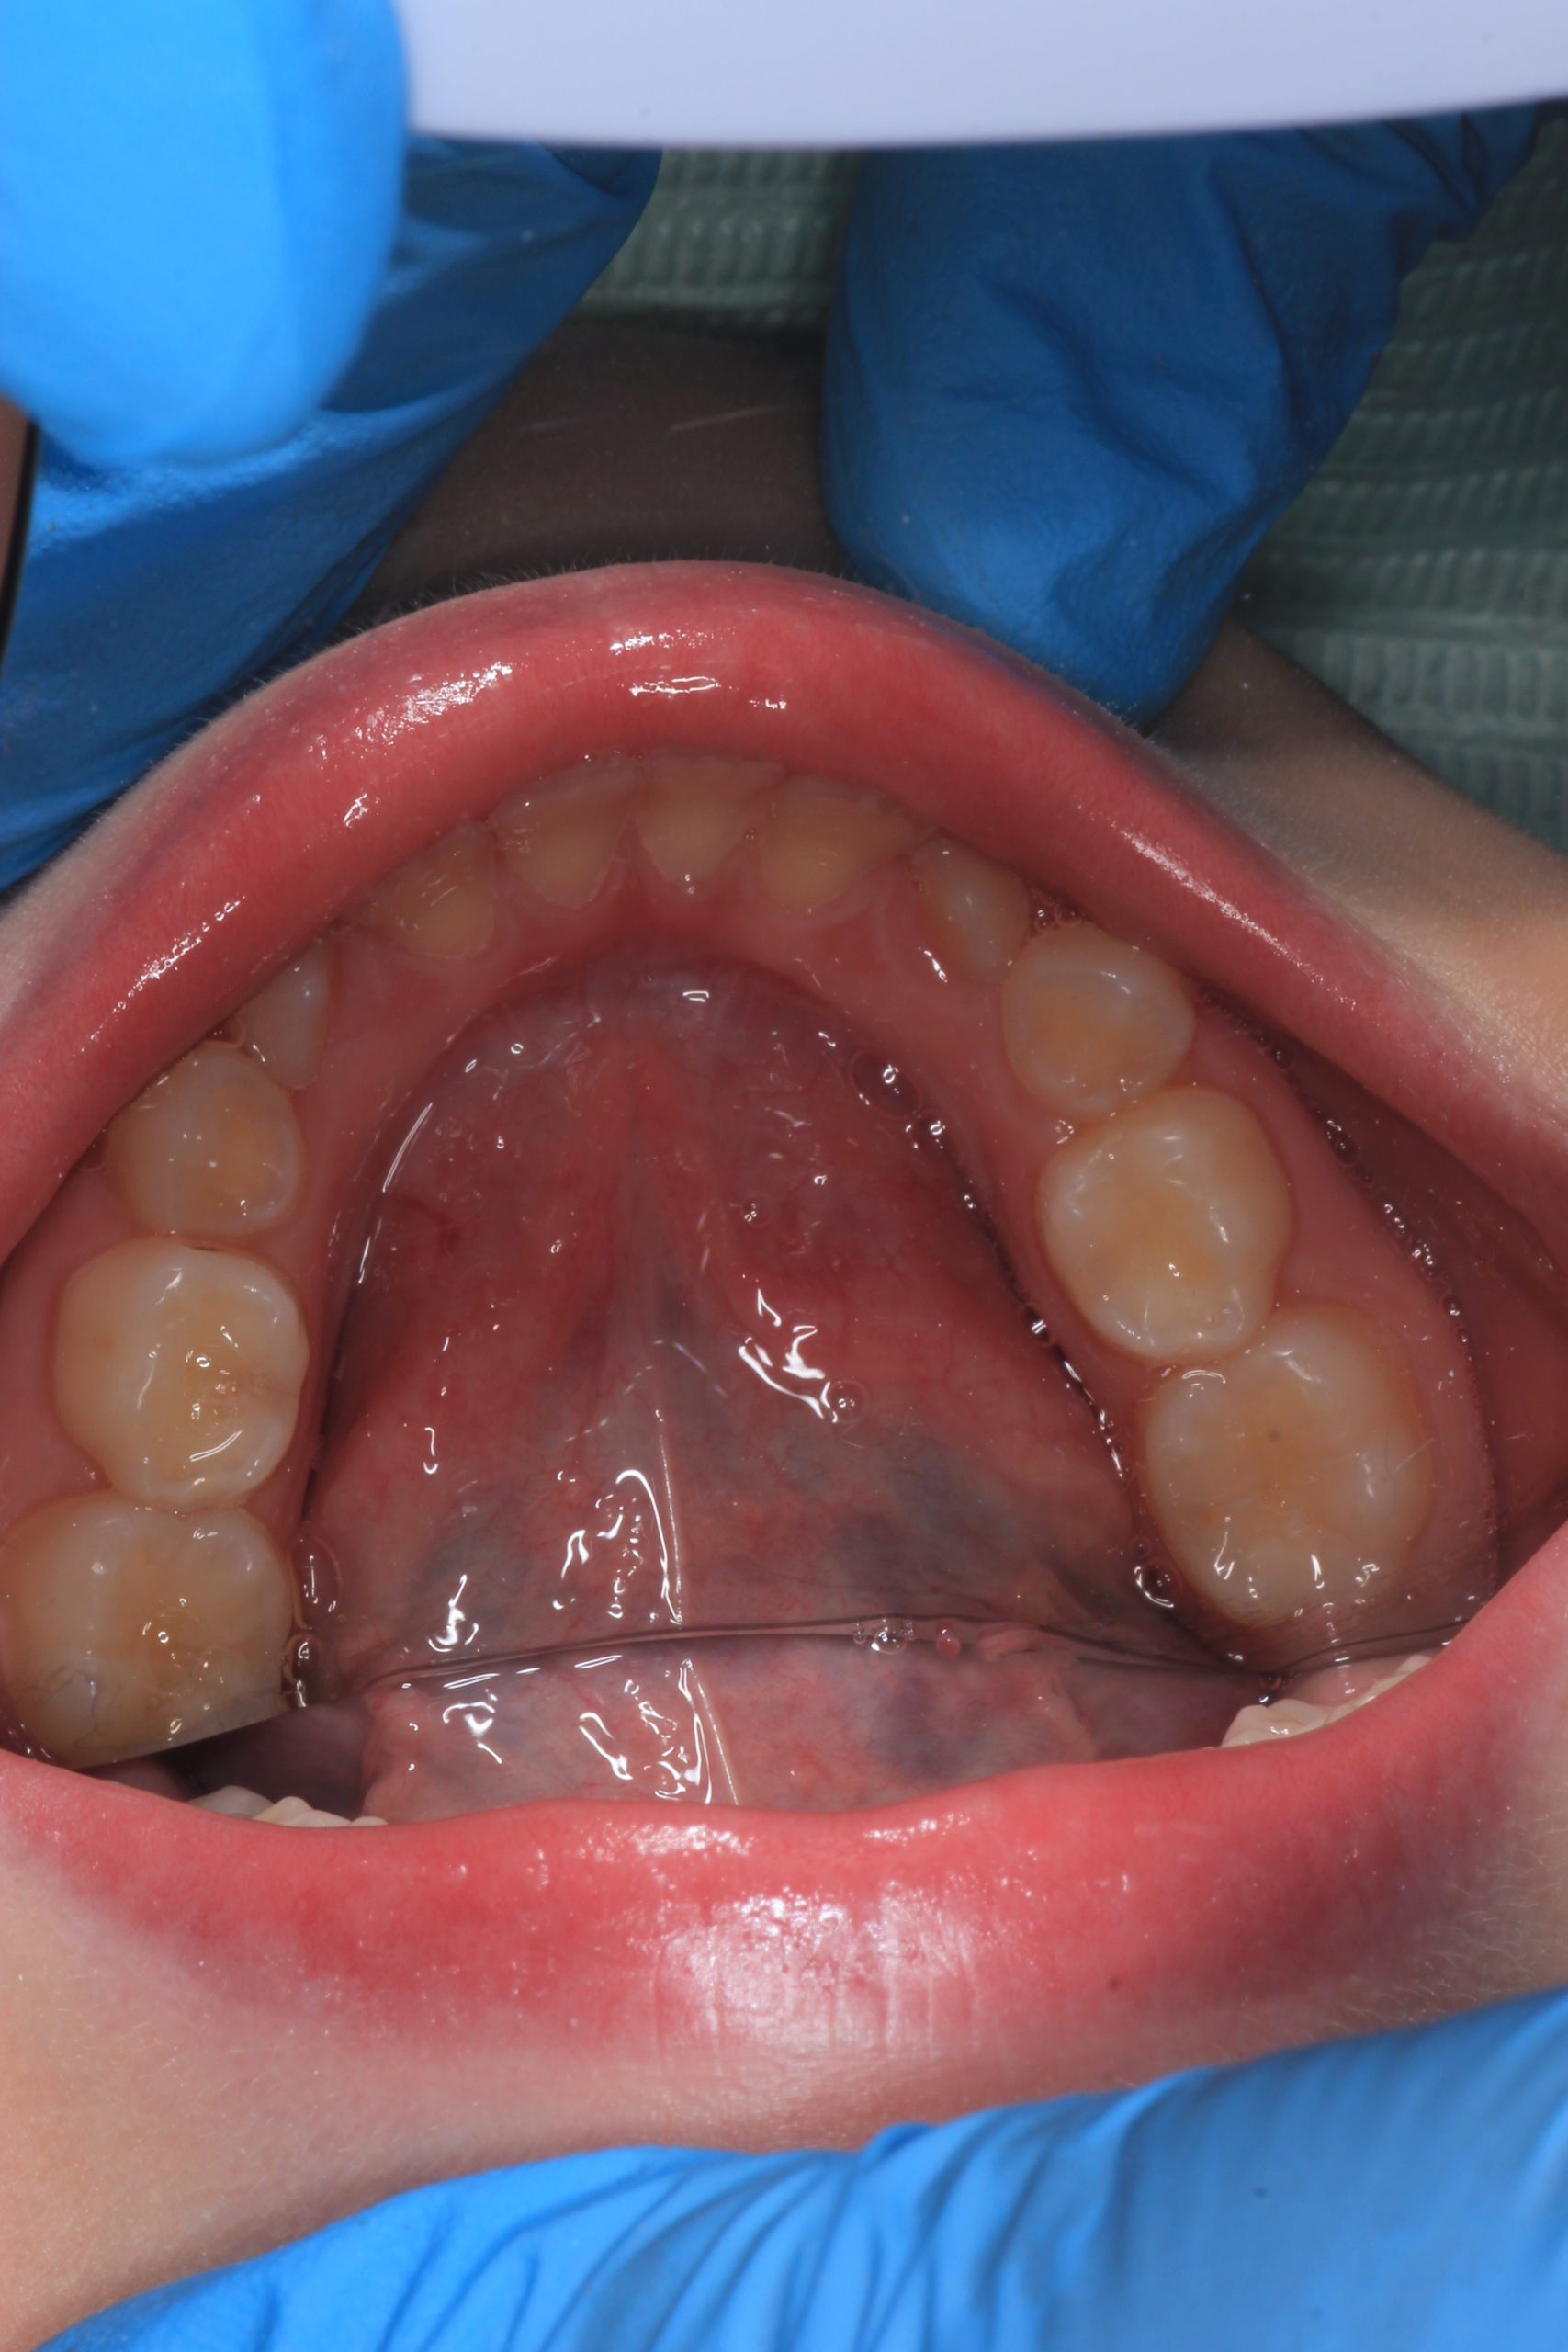

We examine the condition of teeth, gums, and bite. - Plaque Disclosure with Special Indicators

Areas that weren’t cleaned well appear purple. The darker the shade, the older the plaque. This helps both kids and parents understand where brushing needs to improve. - Brushing Training & Home Care Tools Selection